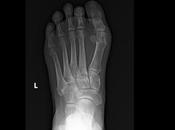

Existe fractura a nivel de proceso posterior del astrágalo con edema asociado

RADIOGRAFIA AP Y LATERAL DE TOBILLO LAS PROYECCION RADIOLOGICA OBTENIDA NOS MUESTRA LOS SIGUIENTES HALLAZGOS -Tejidos blandos, con aumento la sede grosor a nive... Leer el resto